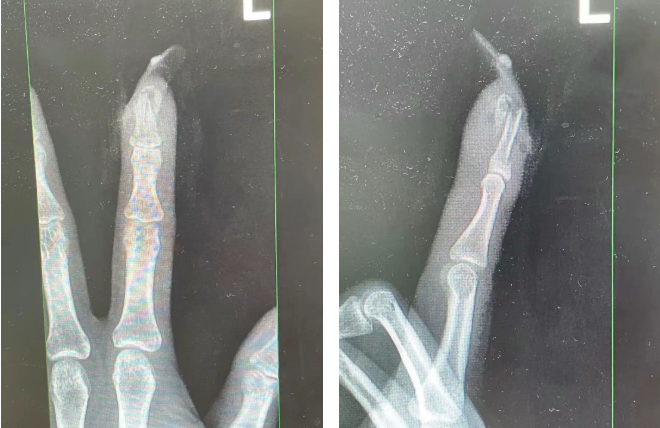

王女士受伤手指的X光影像。图源:杭州市临平区中西医结合医院

经检查

王女士指甲断裂,部分甲床外露

医生表示如果没有美甲

伤害不会这么严重

万幸经过手术

王女士恢复良好